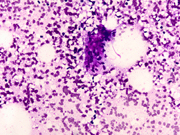

A 64 year old postmenopausal female presented with a 1.5 cm mass in the upper, outer quadrant of her left breast. On mammography this was an isodense lobulated mass. Ultrasonography revealed a solid, hypoechoic complex cystic mass. The patient underwent a fine needle aspiration.

• Fig 2: FNA cytology, Diff-quik stain, X200

Cytologic findings

• Moderately cellular smear

• Branching clusters of ductal epithelial cells, dissociated single cells, or rarely acinar or papillary arrangements

• Polygonal to round ductal epithelial cells with uniform nuclei, abundant cytoplasm and inconspicuous nucleoli

• Focal marked atypia may be seen in benign adenomyoepitheliomas (1).

• Abundant myoepithelial cells as round to spindled shaped cells, as bare oval nuclei in the background or overlying epithelial cell clusters, or as cells with clear cytoplasm

• Focal aggregates of spindled cells

• Fragments of myxoid or fibrous stroma

• Intranuclear inclusions (1) and intracytoplasmic vacuoles (2) have been described

• Thin proteinaceous debris, histiocytes and apocrine cells may be seen

Discussion: Adenomyoepithelioma was first reported by Hamperl in 1970 as an uncommon biphasic tumor composed of epithelial and myoepithelial cells (3). Adenomyoepitheliomas usually present as a single circumscribed mammary nodule. The fine needle aspiration findings in adenomyoepitheliomas have been described in only a few reports (1, 2, 4-11). It is important to recognize this entity as the radiologic and cytologic features can mimic malignancy. On cytology single enlarged atypical epithelial cells, presumed to be of myoepithelial origin due to staining with S-100 protein have been noted and led to the erroneous diagnosis of carcinoma (6). Only rarely can this diagnosis be made definitively on fine-needle aspiration biopsy (7). Histologic patterns include the tubular, lobulated and spindle cell variants (12). Biphasic pattern consists of tubules lined by cuboidal or columnar shaped epithelial cells surrounded by myoepithelial cell layer, Malignant adenomyoepitheliomas are usually characterized by cellular pleomorphism, necrosis, high mitotic activity and invasion of the surrounding tissue. Immunohistochemistry illustrates the biphasic nature of adenomyoepitheliomas with staining for low molecular weight cytokeratin and epithelial membrane antigen in the epithelial component and staining for smooth muscle actin, S-100 protein, calponin, p63 and maspin in the myoepithelial cell component (8)